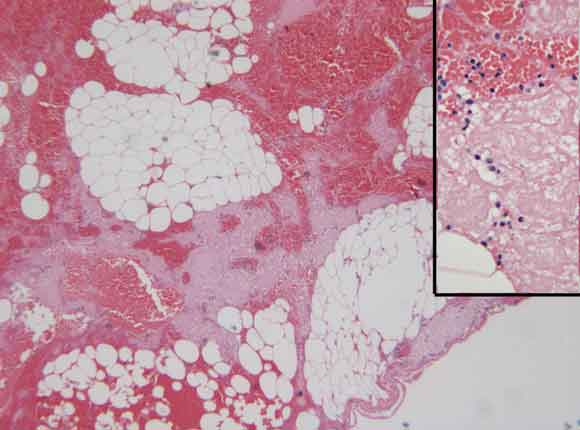

A 44-year-old woman presented with a 3-day history of worsening right upper quadrant pain associated with nausea, anorexia and fever. She had localised tenderness and guarding in the epigastrium. Initial ultrasound imaging showed a distended gallbladder containing calculi, without wall thickening. A computed tomography scan (performed because of increasing pain) showed a whorled structure in the anterior abdomen (Box 1). At laparotomy this was seen to be torsion of a segment of the greater omentum. Histology of the resected specimen showed congestion of the vessels, haemorrhagic infarction and focal fat necrosis (Box 2). She made an uncomplicated and rapid recovery.